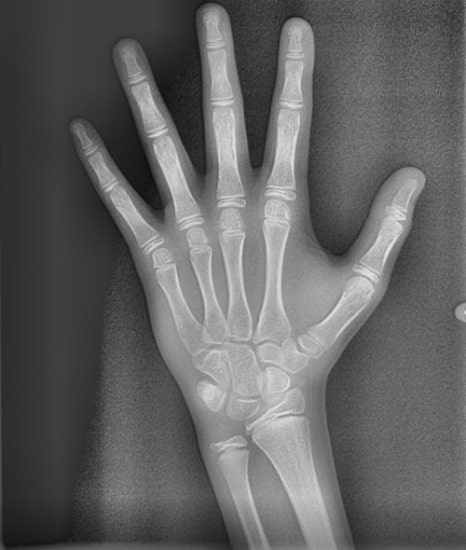

소아 청소년 시기에는 손뼈의 성장판 검사를 통하여 현재의 성장 단계와 향후 남아있는 성장량을 알 수 있으며, 이를 통해 어린이 교정 치료의 적기를 판단하여 교정 치료 방법을 결정하게 됩니다. 연세정원치과에서는 손 엑스레이를 찍은 후 뷰노매드 본에이지 검사를 통해 성장판 검사를 시행합니다. 뷰노매드 본에이지 검사는 손 엑스레이 사진을 판독하여 현재의 뼈나이와 예상 신장을 알려주는 검사입니다. 뷰노매드 본에이지는 약 72.5% 정도의 정확성을 갖는 검사로, 의사가 눈으로 판독했을 때보다 판독 일치도가 15% 이상 향상된 프로그램입니다.

뷰노매드 성장판 검사